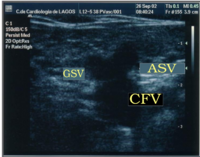

Mickey Mouse sign is a medical sign resembling the head of Mickey Mouse, the Walt Disney character. Presented for the very first time at the CHIVA's Meeting, Berlin 2002 by Dr. Lurdes Cerol, this sign has been described as the image at the groin when a dilated accessory saphenous vein (ASV) exists: the common femoral vein (CFV) represents the head of Mickey Mouse while the great saphenous vein (GSV) and the dilated accessory saphenous vein (ASV) represent the ears. The presence of a Mickey Mouse sign has been a great diagnostic clue to check ASV insufficiency.

Mickey Mouse sign in the saphenofemoral junction, showing GSV, a dilated ASV and CFV

Some authors, inspired by this sign, described an ecographic "Mickey Mouse View" at the saphenofemoral junction in the groin: the common femoral vein (CFV) represents the head of Mickey Mouse while the great saphenous vein (GSV) and the accessory saphenous vein (ASV) represent the ears.[1]